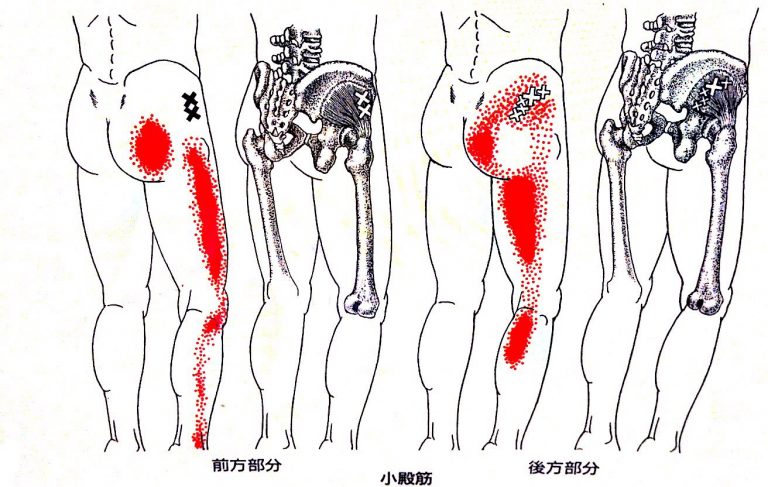

1.小殿筋による腕や手のしびれ

小殿筋は、お尻の深い部分にある筋肉で、歩く・立つ・体を支えるときに重要な働きをしています。

この小殿筋に**トリガーポイント(×印の部分)**ができて固まってしまうと、神経を刺激し、次のような広い範囲に痛みが出ることがあります。

- お尻の奥の痛み

- 太ももの外側のしびれ・痛み

- ふくらはぎまで響くような違和感

赤い部分のように、脚全体に痛みが放散する坐骨神経痛タイプで、「太ももの横が痛い」「歩くと脚にズーンと痛みが出る」という方に多く見られます。

小殿筋が原因の坐骨神経痛は、筋肉がしっかりほぐれてくると改善が期待できます。